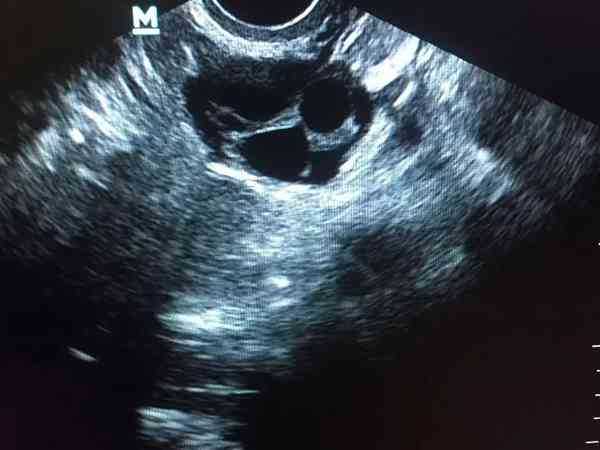

阴道b超检查能不能看出卵泡黄素化?抽血能否看出?

卵泡黄素化一般主要是通过阴道b超可以看出来,当卵泡长大到25mm,如果检测还没有排卵,那可能就是卵泡黄素化,但是有的人优势卵泡就是比较大,排卵晚一些,所以B超如果看到卵泡长到25mm就没有监测了,可能会出现误判。还有就是可以结合人尿中黄体生成素的检查来确定,也可以结合基础体温来进行判断,抽血化验看雌孕激素水平也可以,但无论是哪种方式,都不能做到100%准确。卵泡黄素化就是卵泡不破不排卵而原位黄素化...